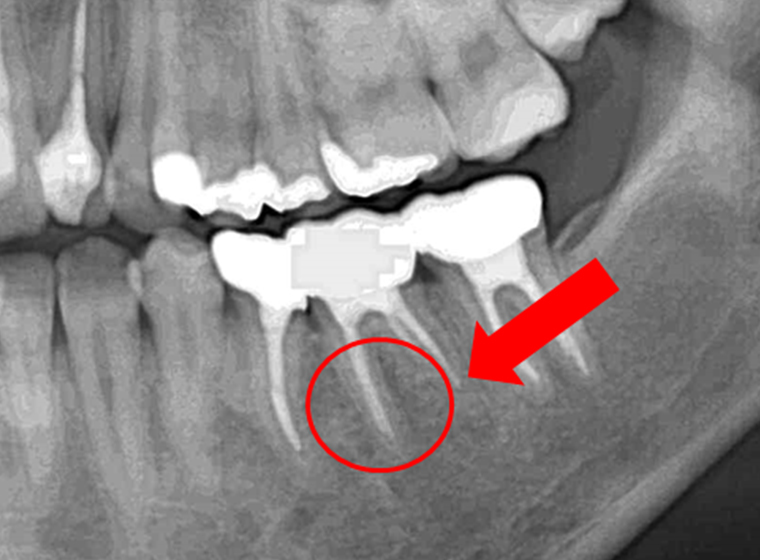

奥歯の症例

それぞれ、左が術前で右歯術後の写真です。根の先に大きな膿のかたまり「根尖病巣」ができており、噛めないくらいの強い痛みと腫れがありました。術後は根尖上病巣が消失し、不快症状もありません。根管治療後に歯根の先端まで白く写っていて、充填材が届いていることが確認できます。抜歯が検討されるくらいの難症例でしたが、「できるだけ歯を抜かない」ことを心がけている当院だからこそできた治療です。